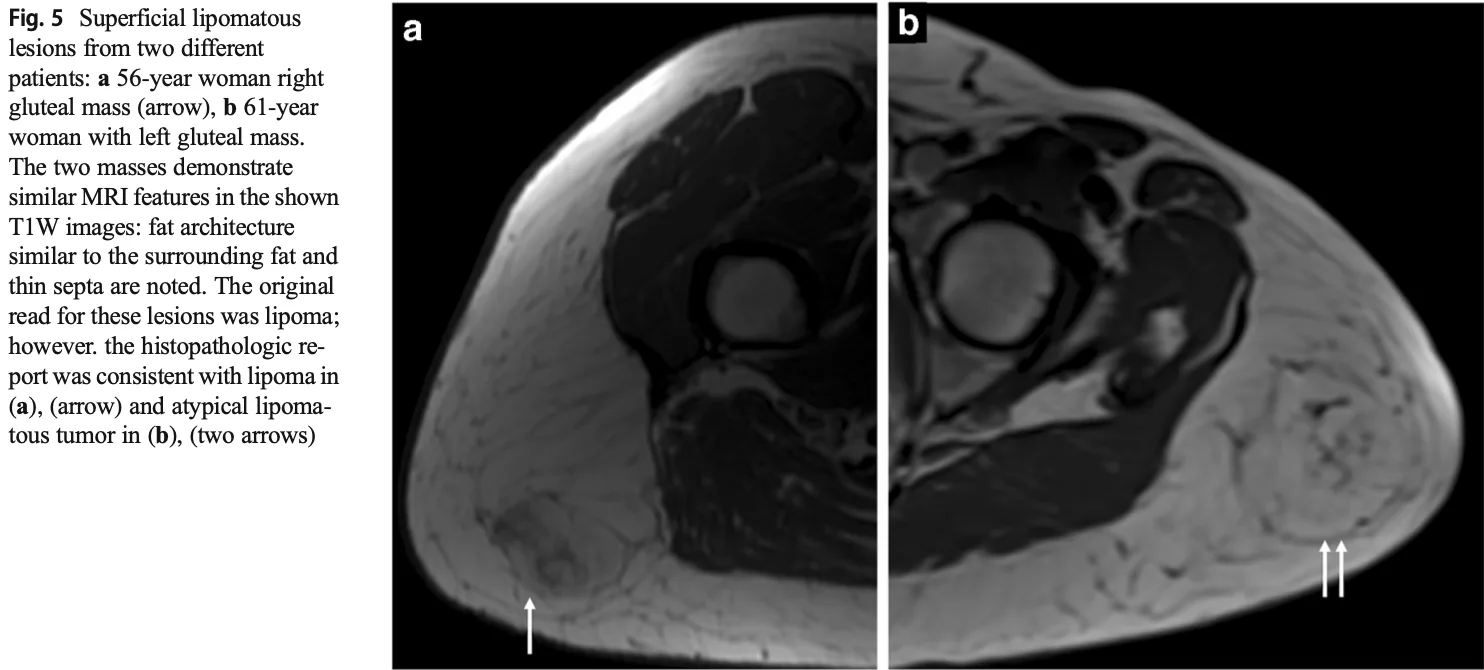

aは良性の脂肪腫, bは良悪性中間型の異型脂肪腫様腫瘍.

どちらも皮下脂肪との境界が不明瞭です.

MRIを撮像した結果, 皮下脂肪の肥厚を認めるものの, 腫瘍の再発かどうかは判断できませんでした.